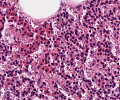

Mastopathie.png

Mammagewebe mit zystischer Aufweitung der Drüsen mit abgeflachtem Drüsenepithel (links oben) und zystischer Aufweitung des Gangepithels (rechts daneben)

Mastopathie1.png

Zystische Aufweitung des Gangepithels mit apokrinen Metaplasien